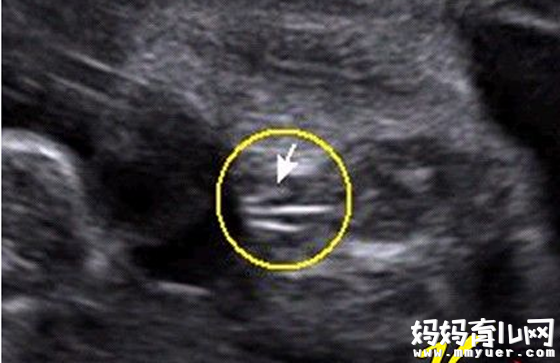

女宝宝的b超图:

三条白线是明显的女宝特征,如果没有看到明显的三条白线,就看两腿之间有没有突出的东东,且中间有小凹槽的,就是女宝